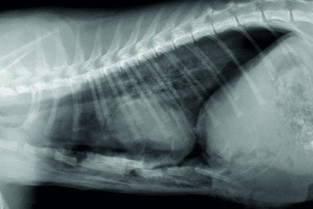

Le GEIM vous propose une séance de travaux pratiques de radiographies sur le thorax. Tous les aspects sont abordés sous la forme de TP de lecture de radiographies numériques sur station de travail Osirix sur Mac (3 vétérinaires maximum/ordinateur).

- adopter une méthodologie pour interpréter les affections pulmonaires chez les carnivores domestiques ;

- connaître l’aspect normal et anormal des poumons chez les carnivores domestiques.